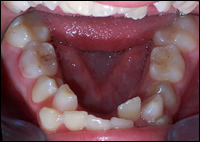

Fig 1 & 2: An 11 year old female presented with a narrow upper and lower dental arches and crowded teeth.